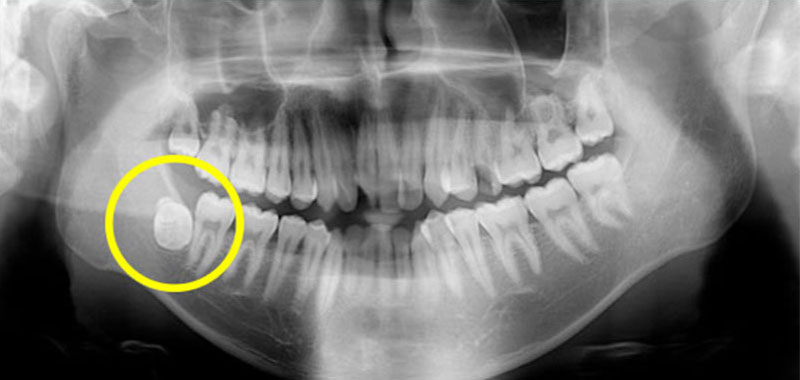

右邊下顎埋在骨頭內的智齒